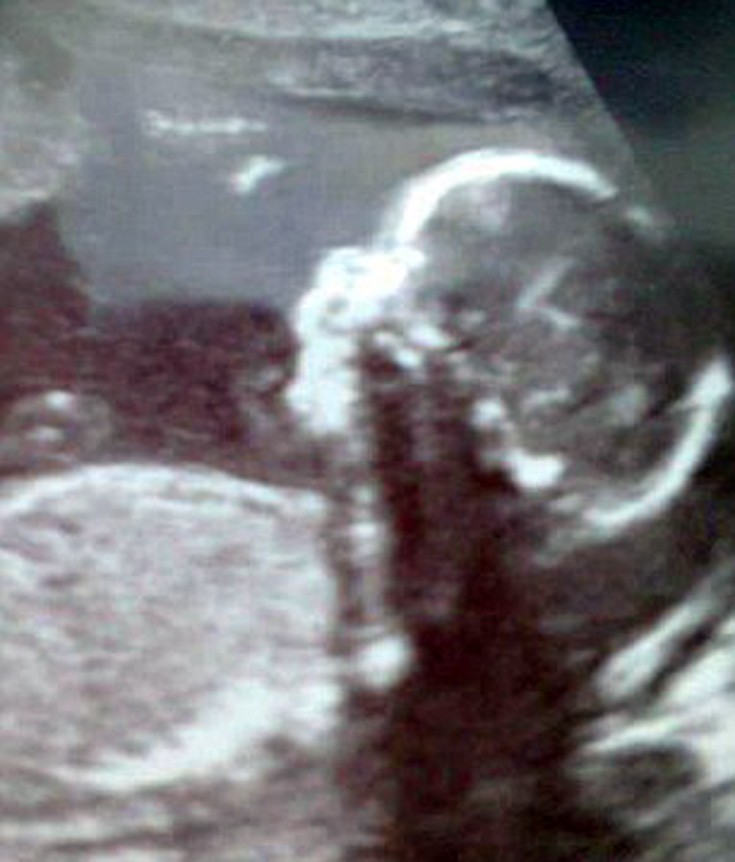

Η μητέρα ανακάλυψε για πρώτη φορά το πρόβλημα κατά την εγκυμοσύνη της, με υπέρηχο στις 20 εβδομάδες. Οι γιατροί της είπαν ότι είχε έναν μαλακό ιστό που αναπτυσσόταν στο πρόσωπό του. «Όταν μου έδωσαν τον Ollie να τον κρατήσω, ήμουν τόσο έκπληκτη που σχεδόν δεν μπορούσα να μιλήσω», λέει η μητέρα που έχει χωρίσει με τον πατέρα του παιδιού. «Ήταν τόσο μικρός, αλλά δεν υπήρχε αυτή η τεράστια μπάλα σε μέγεθος μπάλας γκολφ στη μύτη του. Στην αρχή δεν ήμουν σίγουρη πώς θα αντιμετώπιζα την κατάσταση. Αλλά ήξερα ότι θα τον αγαπούσα και δεν έχει σημασία πώς θα έμοιαζε», αναφέρει στη συνέντευξή της.

Μια μαγνητική τομογραφία επιβεβαίωσε αργότερα ότι επρόκειτο για μια εγκεφαλοκήλη, μια γενετική διαταραχή που κάνει τον εγκέφαλο να αναπτύσσεται μέσα από μια τρύπα στο κρανίο, δημιουργώντας ένα σάκο που προεξέχει. Στην περίπτωση του μικρού αγοριού ο σάκος δημιουργήθηκε στη μύτη του. Κατά τη διάρκεια των πρώτων 9 μηνών ο σάκος μεγάλωνε, όσο μεγάλωνε και ο μικρός Ollie.